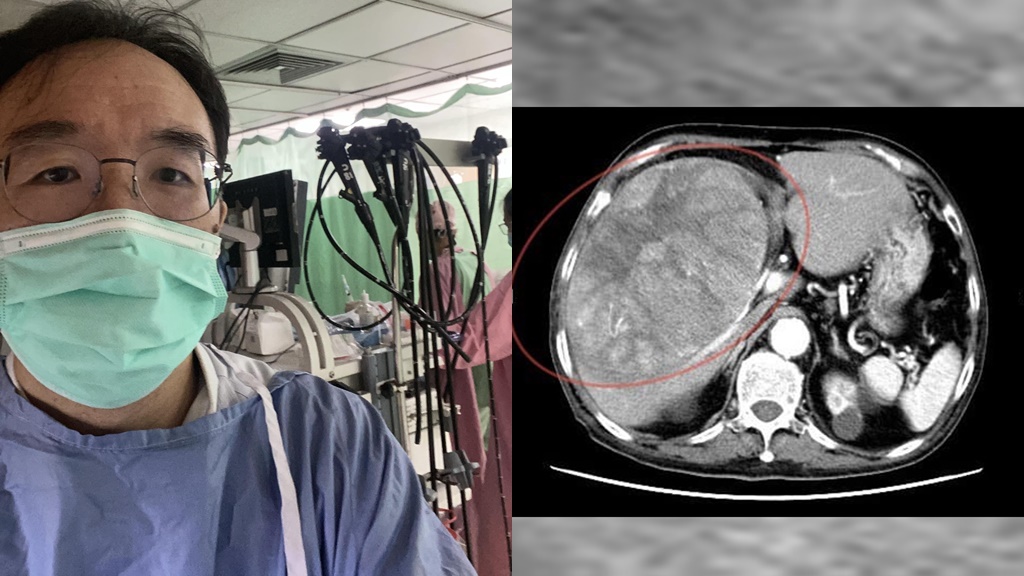

直到2個多月前,老翁開始出現上腹疼痛和胃酸逆流的症狀,前往錢政弘的門診求診。錢政弘發現,疼痛位置偏右上腹部,且右側肋骨下方有壓痛,懷疑是膽囊問題,安排腹部超音波檢查,卻意外發現肝臟有一個15公分大的腫瘤。

原來老翁腹部按壓會痛的部位,其實是巨大的肝癌,甚至用手從外部就能觸摸到。後續電腦斷層檢查證實,已是晚期肝癌,無法手術治療。

◎ 圖片來源/翻攝自錢政弘醫師臉書